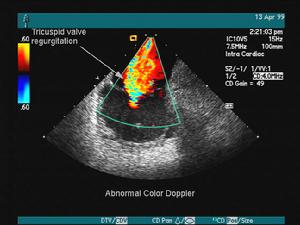

心臟彩超

心臟彩超心臟超聲可以對心臟形態、室壁運動以及左心室功能進行檢查,是目前最常用的檢查手段之一。血管內超聲可以明確冠狀動脈內的管壁形態及狹窄程度,是一項很有前景的新技術。